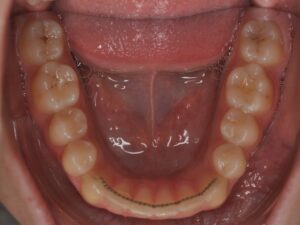

- d’un fil collé sur la face interne (linguale) des dents

Le fil de contention quant à lui est fixe. Idéalement, il est à garder toute votre vie également.

Les deux premières années il est conseillé de contrôler ses contentions tous les 3-4 mois.

Puis une fois par an lorsqu’il n’y a pas de soucis.